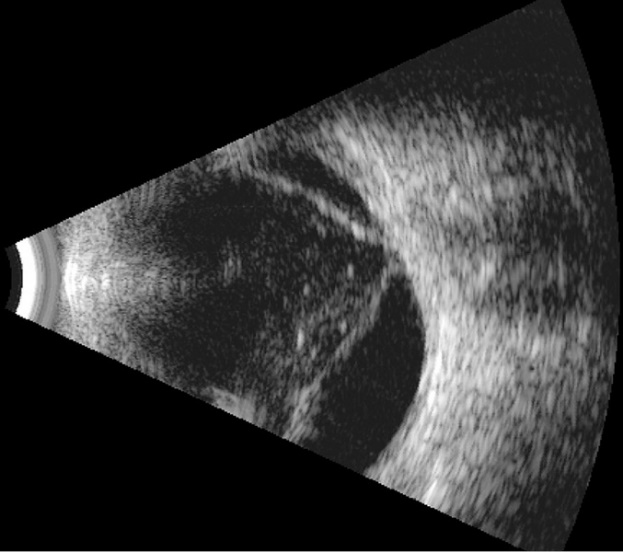

USG oka – prezentacja B

USG oka prezentacja B

Nieinwazyjna metoda badania, nie wymaga przygotowania

Badanie wykonuje się przy zamkniętych powiekach po nałożeniu żelu kontaktowego

Badanie ocenia tylny odcinek oka i jest kluczowe przy niedostatecznej przezierności

ośrodków optycznych oka (np. zaćma czy wylew krwi do ciała szklistego).

USG oka wykrywa nieprawidłowości wewnątrz gałki ocznej i oczodole, takie jak

odwarstwienie siatkówki, guzy wewnątrzgałkowe, krwotoki do ciała szklistego czy

obecność ciał obcych.Pomaga także monitorować zmiany u pacjentów z cukrzycą.

Co może wykryć USG oka:

- Odwarstwienie siatkówki: Jedno z głównych zastosowań, które pozwala ocenić ten stan, gdy badanie dna oka jest utrudnione,

- Guzy wewnątrzgałkowe: Umożliwia wykrycie i określenie lokalizacji oraz wielkości guzów,

- Krwotoki: Pozwala zdiagnozować wylewy krwi do ciała szklistego lub do wnętrza oka,

- Ciała obce: Pomaga zlokalizować obecność ciał obcych wewnątrz oka,

- Zmiany w nerwie wzrokowym: Może ujawnić np. druzy czy obrzęk nerwu wzrokowego,

- Stany zapalne: Pozwala ocenić przebieg stanów zapalnych w oku, np. zapalenie tylnej twardówki czy garbiaka twardówki,

- Zmiany proliferacyjno- krwotoczne w cukrzycy,

- Powikłania pooperacyjne: Pomaga ocenić stan oka po zabiegach operacyjnych,

- Zmiany w soczewce: Wykrywa zmiany w strukturze soczewki.